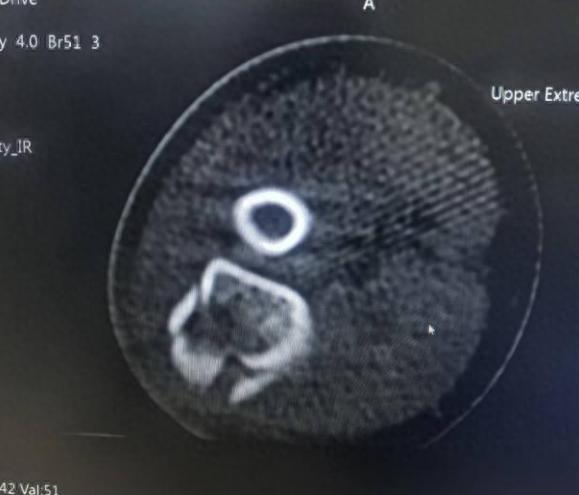

张同学,8岁,在学校上体育课时失慎跌倒,右手肘撞击大地。CT败露:尺骨鹰嘴骨折。浩荡医师平直提议手术,用钢针进行内固定。意义是,要津内骨折及要津周围骨折,术后能早起功能熟识退缩要津粘连。孩子据说要手术吓得哭了起来,带着张惶,张同学及家长来到了滨州市中医病院骨伤科(创伤)门诊。

大夫通过属看法阅片和身段查验,发现张同学的骨折隐微移位,经过崇拜考量,为张同学制定了一套“组合拳”式的保守救援决议,中枢在于 “手法复位、弹性固定、中西齐集、功能熟识”。